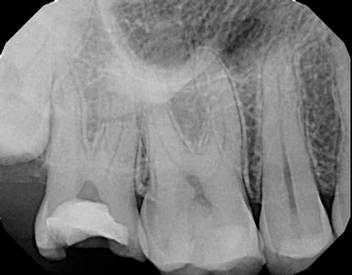

Periapical imaging revealed evidence of a prior pulpotomy on tooth No. 2, without obvious signs of apical pathology (Figure 5). A deep restoration with evidence of periapical pathology was seen on periapical imaging of tooth No. 30 (Figure 6). The diagnosis for tooth No. 2 was previously initiated treatment with normal periapical tissues, while the diagnosis for tooth No. 30 was pulpal necrosis with symptomatic apical periodontitis. Although it was clear that both teeth would eventually require definitive endodontic treatment or extraction, the source of the current severe pain remained unclear.

Fig 5. Case 2: Periapical imaging of the maxillary right (Fig 5) and mandibular right (Fig 6) quadrants.

Figure 5

Fig 6. Case 2: Periapical imaging of the maxillary right (Fig 5) and mandibular right (Fig 6) quadrants.

Figure 6